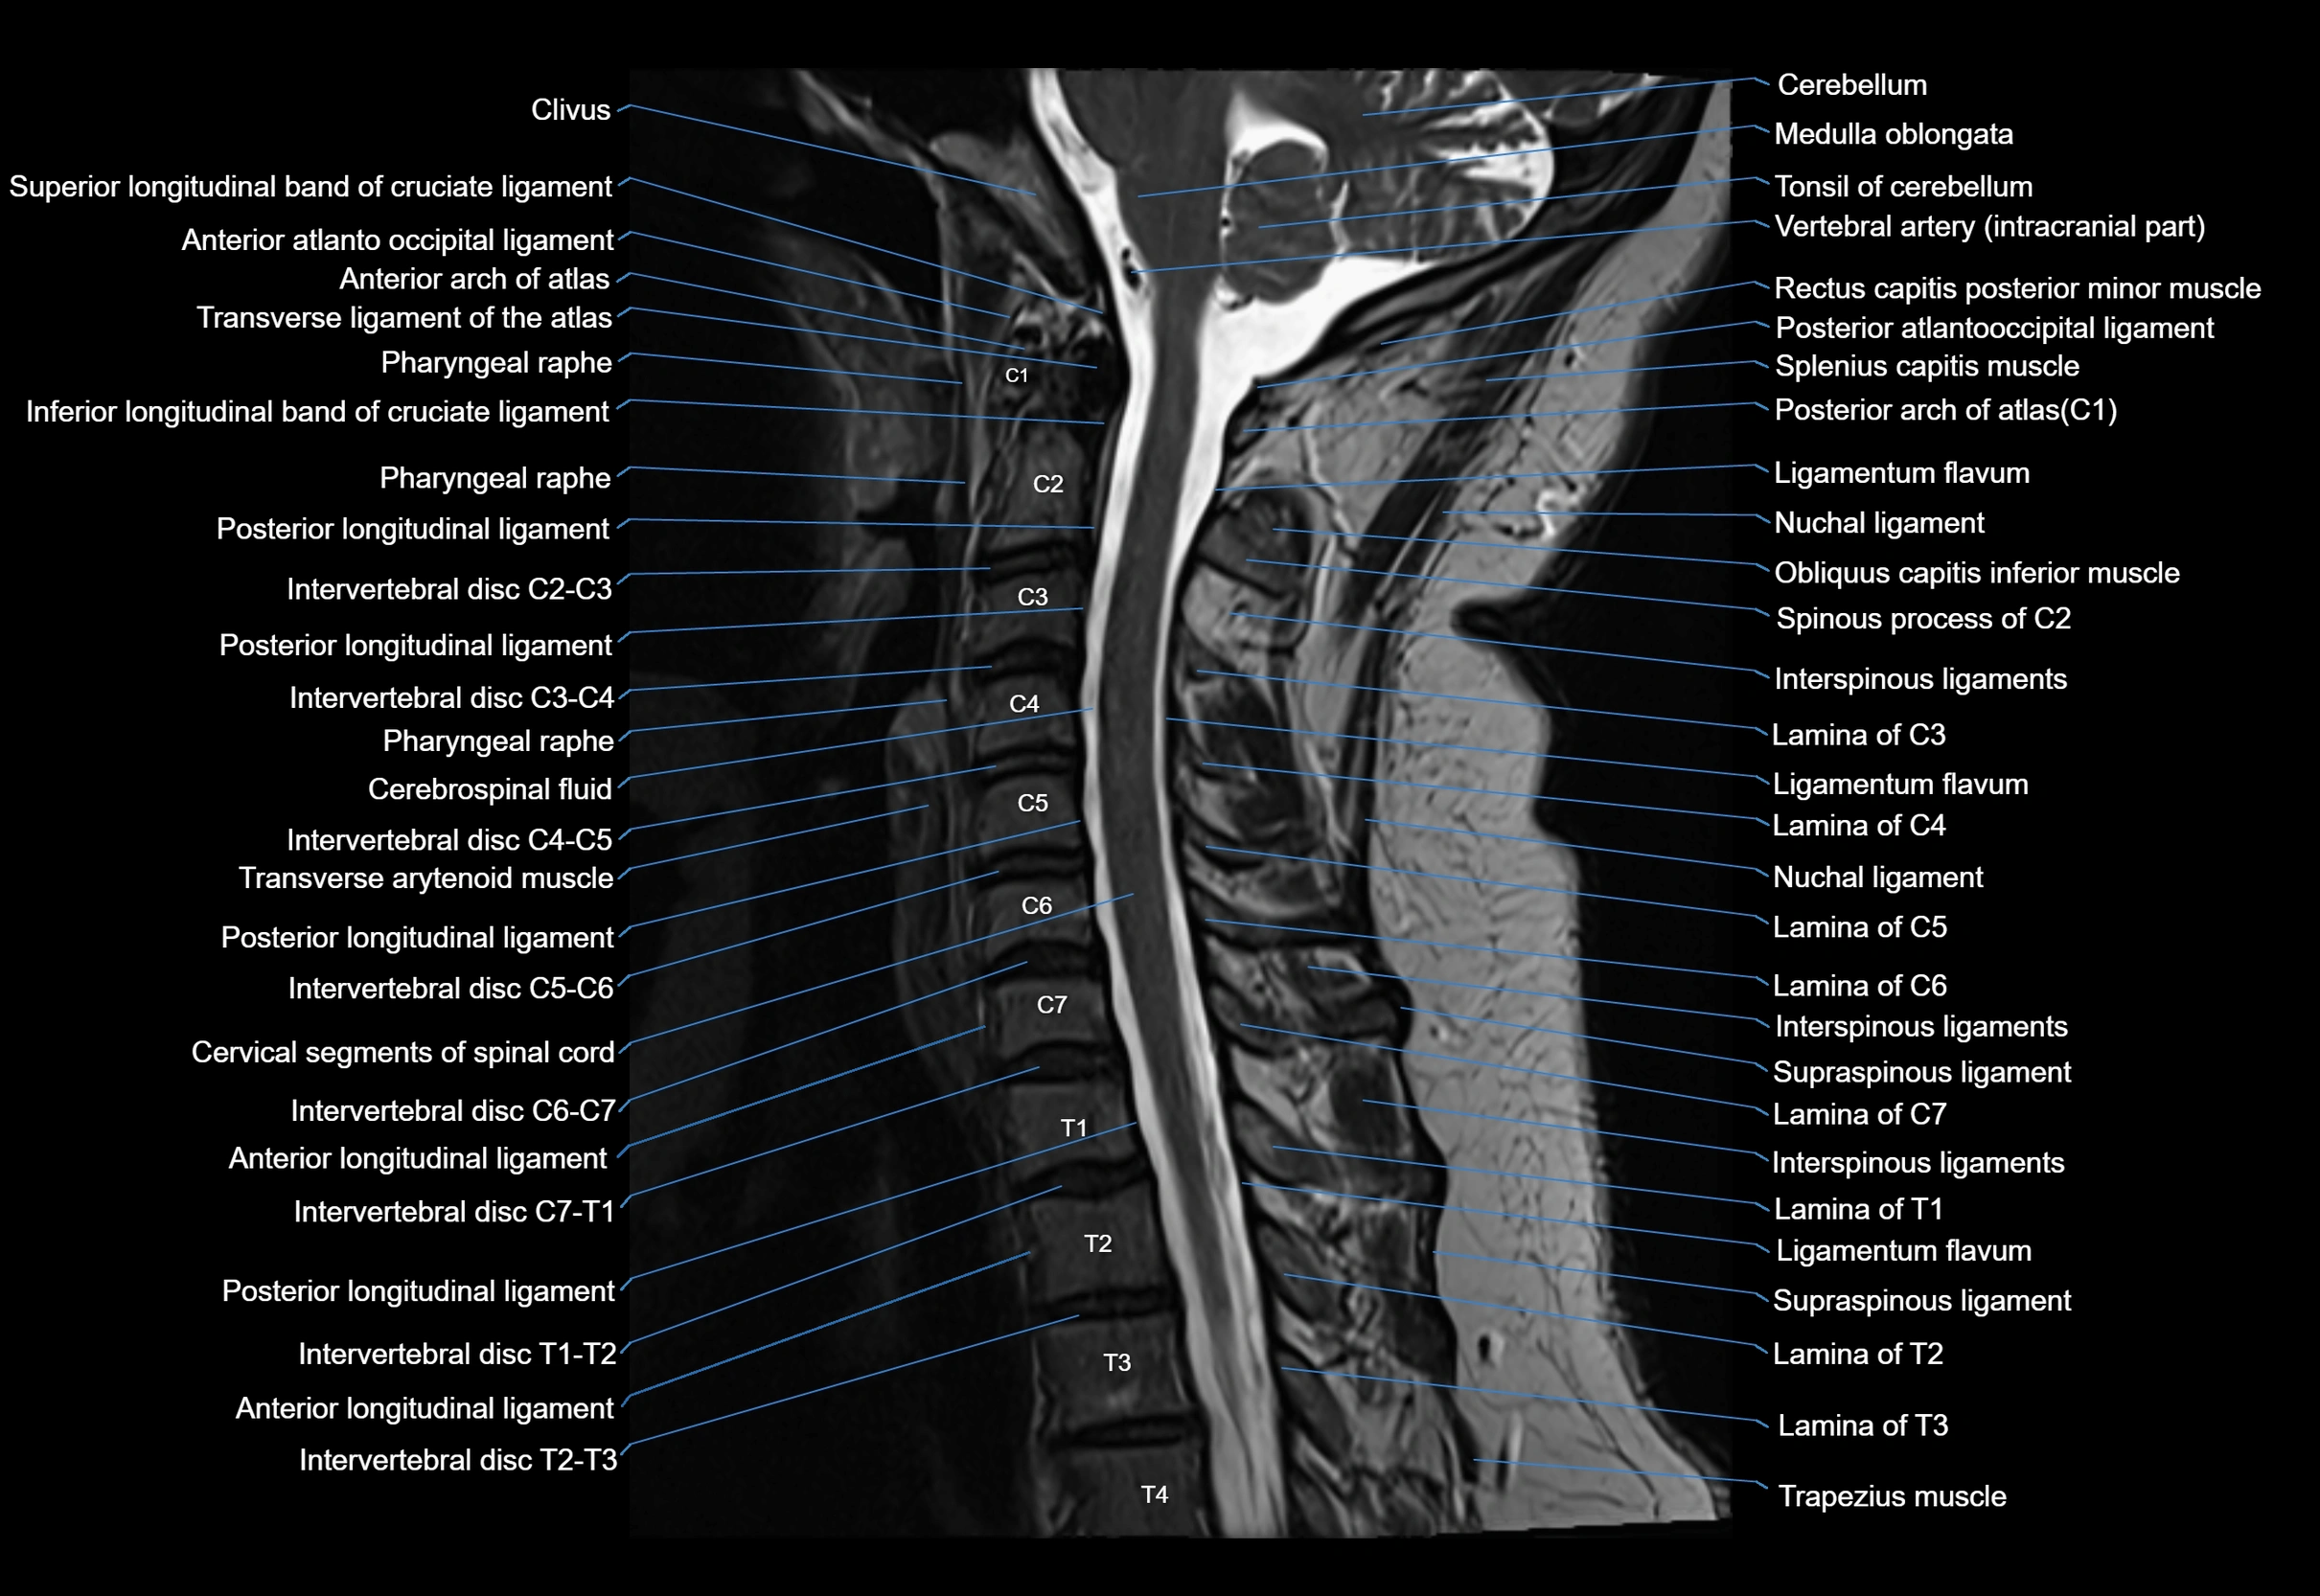

• Anteriorly: Anterior longitudinal ligament (ALL) reinforces the annulus

• Posteriorly: Posterior longitudinal ligament (PLL) lies along its posterior aspect